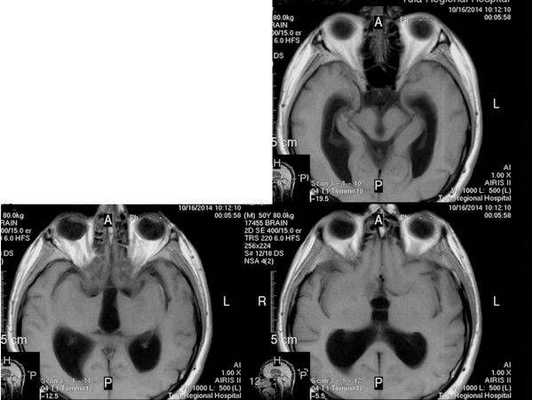

- МРТ в динамике показывает постепенное сужение желудочковой системы на 2 мм. Для сравнения представлены снимки МРТ от 14.05.2013 и от 16.10.2014.